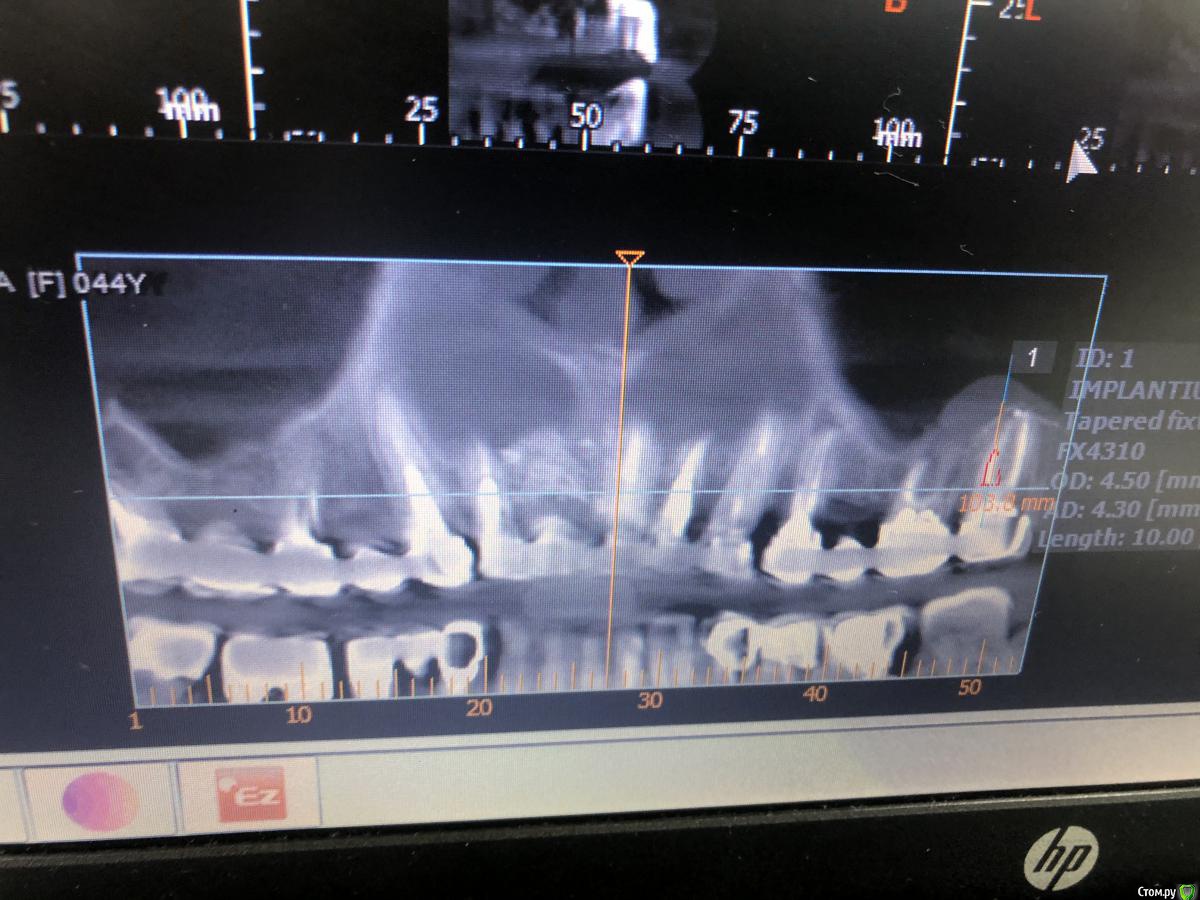

Александр07 Опубликовано 14 августа, 2020 Автор Поделиться Опубликовано 14 августа, 2020 Коллеги планируется имплантация на вч-удаление 2.4,2.6, 2.7 под ? ( ферула нет после снятие мк, можно попробовать удлинить но ортопед не особо настроен ) , здесь сложность в том что пац не может ходить без зубов, чтобы окружающие не знали об этом, Первый вариант это удаление 2.4-2.6 и капа , второй вариант это убрать 2.4,26.2,7 и импл с нагрузкой 2.4,2.5, 2.7 Вот срезы, скажите что думаете , насколько вероятно нагрузить и стоит ли, в обл 2.5 по хорошему откр с лифт, можно попробовать закрытый, 2.7 придётся смещать к перегородке межзубной Ссылка на комментарий

Nazim_NV86 Опубликовано 4 июля, 2020 Поделиться Опубликовано 4 июля, 2020 (изменено) Как расположить такой винт, чтобы не соприкасался с имплантом? Таблетку под углом к импоанту?1.Типа того2.У вас ФИО пациента видно. Желательно обрезать, то что выкладываете в сеть.3.Скачайте с оф сайта планмеки нормальную бесплатную версию. Там уже 6-я версия с мая этого года. И главное что ваш нарисованный план будет сохраняться. Изменено 4 июля, 2020 пользователем Nazim_NV86 2 Ссылка на комментарий

Nazim_NV86 Опубликовано 8 июля, 2020 Поделиться Опубликовано 8 июля, 2020 СпасибоЗдесь больше похоже на миниблок)Это бета-версия. Ссылка на комментарий